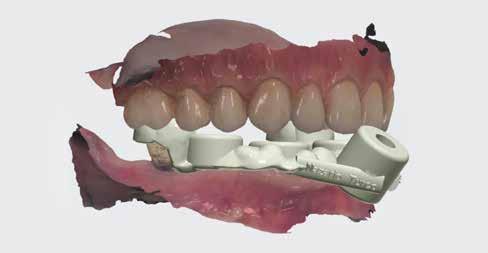

Rögtön a sebészeti eljárást követően a BioHorizons szkennelő fejeket felpattintottuk, és a lágy szövetek zárását követően megtörtént a 3shape digitális intraorális lenyomatvétel. Pontosabbnak tartom ezt a változatot, mint a fogpótlás és az implantátumok egyidejű tervezését. Vannak olyan tűréshatárok, amelyek befolyásolhatják a paszszív illeszkedést több implantátum használatának esetében (17. kép).

Az okklúzió és a szkennelő fejek háromdimenziós térbeli környezetben történő beszkennelésének képessége lehetővé teszi, hogy ez a munkafolyamat sokkal pontosabb és időtakarékosabb legyen az analóg munkavégzésnél (18-20. kép).

Az ideiglenes híd elkészítéséhez szükséges műtét előtti szkennelés rendkívüli módon lehetővé teszi a páciens foghúzás előtti állapotának pontos másolatát. A húzás előtti felvétel készítésének lehetősége, ahol az okklúziót be tudtuk szkennelni, a digitális munkavégzés könnyed protetikai munkát biztosít a teljes kezelési folyamat részeként (2122. kép).

Ezután egy azonnali ideiglenes hidat készítettünk elfordulásgátló-mentes, ideiglenes bázisokra (23-24. kép). A kezelési terv az volt, hogy PMMA-ból készítjük a hídvázat rózsaszín kompozittal és festéssel kiegészítve.

Megkezdődött a CAD dizájn kialakítása Bradley Grobler fogtechnikai kerámiás szakember által. Látható a képen, hogy az összes információt/adatot egy képernyőre vetítve, a fogpótlás tervezése szintén nagyon egyszerű (25. kép).

18-20. kép: 3shape intraorális szken felvételek a sebészetet követően.

21-22. kép: A preoperatív felvétel szuperpozíciója az implantátumokról készült felvételen.